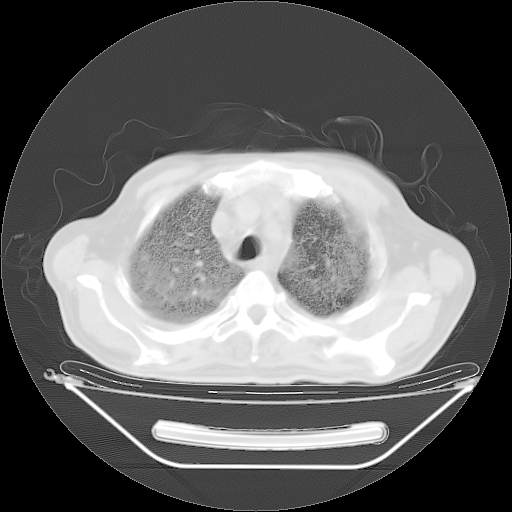

今天复查肺部CT,发现双肺广泛磨玻璃样改变。所以我把3月19日和5月9日相隔50天的肺部CT上传。请大家会诊。

5月9日肺部CT(在4月27日齐鲁医院肺部CT描述部分肺组织磨玻璃样改变,12天后肺组织广泛磨玻璃样改变)

大致读了系列胸部CT:纵隔窗无明显异常,肺窗:从4、27至今:主要是双肺中下野外带可见毛玻璃样改变,目前处于急性肺泡炎阶段,至于原因考虑1、结替组织或胶原血管性疾病所致?2、恶性疾病如恶组在肺部所致的表现或细支气管肺泡癌?3、药物或其它原因如肺蛋白沉着症所致肺泡炎目前不太可能?总之,明天就去请我院的呼吸科、感染科、血液科和临免专家会诊哈。